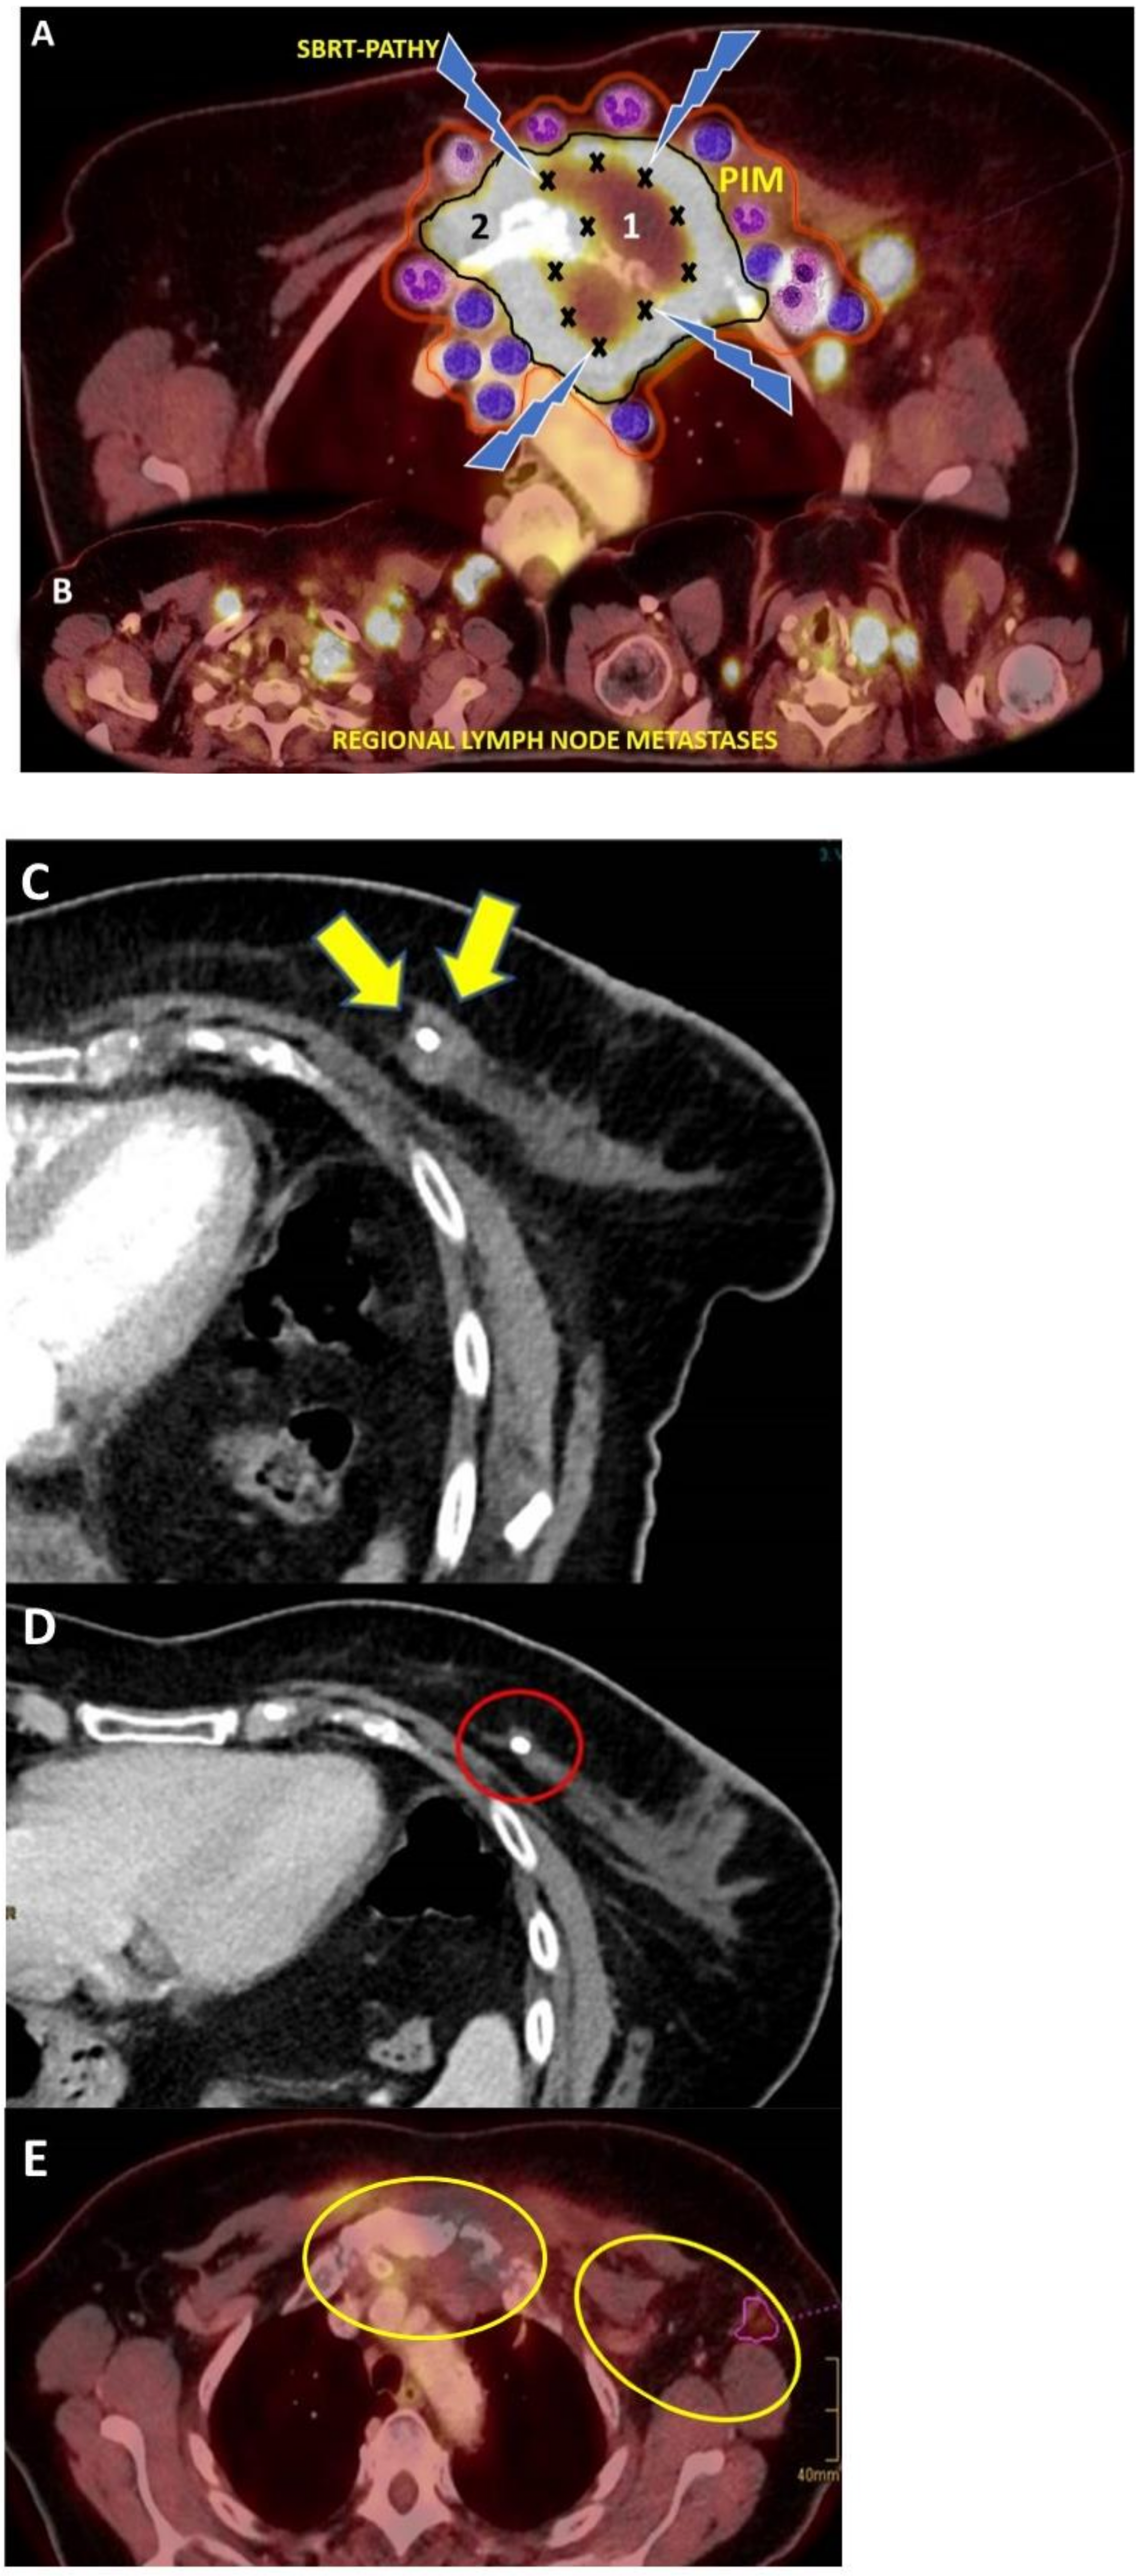

- Tubin, S.; Khan, K.M.; Salerno, G.; Mourad, W.F.; Yan, W.; Jeremic, B. Mono-institutional Phase II study of innovative stereotactic body radiotherapy targeting partial tumor hypoxic (SBRT-PATHY) clonogenic cells in unresectable bulky non-small cell lung cancer: Profound non tar-geted effects by sparing peri-tumoral immune microenvironment. Radiat. Oncol. 2019, 14, 212. [Google Scholar]

- Tubin, S.; Popper, H.; Brcic, L. Novel stereotactic body radiation therapy (SBRT)-based partial tumor irradiation targeting hypoxic segment of bulky tumors (SBRT-PATHY): Improvement of the radiotherapy outcome by exploiting the bystander and abscopal effects. Radiat. Oncol. 2019, 14, 21. [Google Scholar] [CrossRef] [PubMed]

- Tubin, S.; Ashdown, M.L.; Jeremic, B. Time-synchronized immune-guided SBRT partial bulky tumor irradiation targeting hypoxic segment while sparing the peritumoral immune microenvironment. Radiat. Oncol. 2019, 14, 1–7. [Google Scholar] [CrossRef]